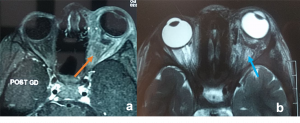

Traumatic carotid-cavernous fistula) Axial T2WI MRI of right orbit showing dilated superior ophthalmic vein along its whole course (orange arrow) b) Coronal T2WI MRI showing dilated superior ophthalmic vein (white dotted arrow) with engorgement of the extra ocular muscles compared to the contralateral normal side (orange arrows) |